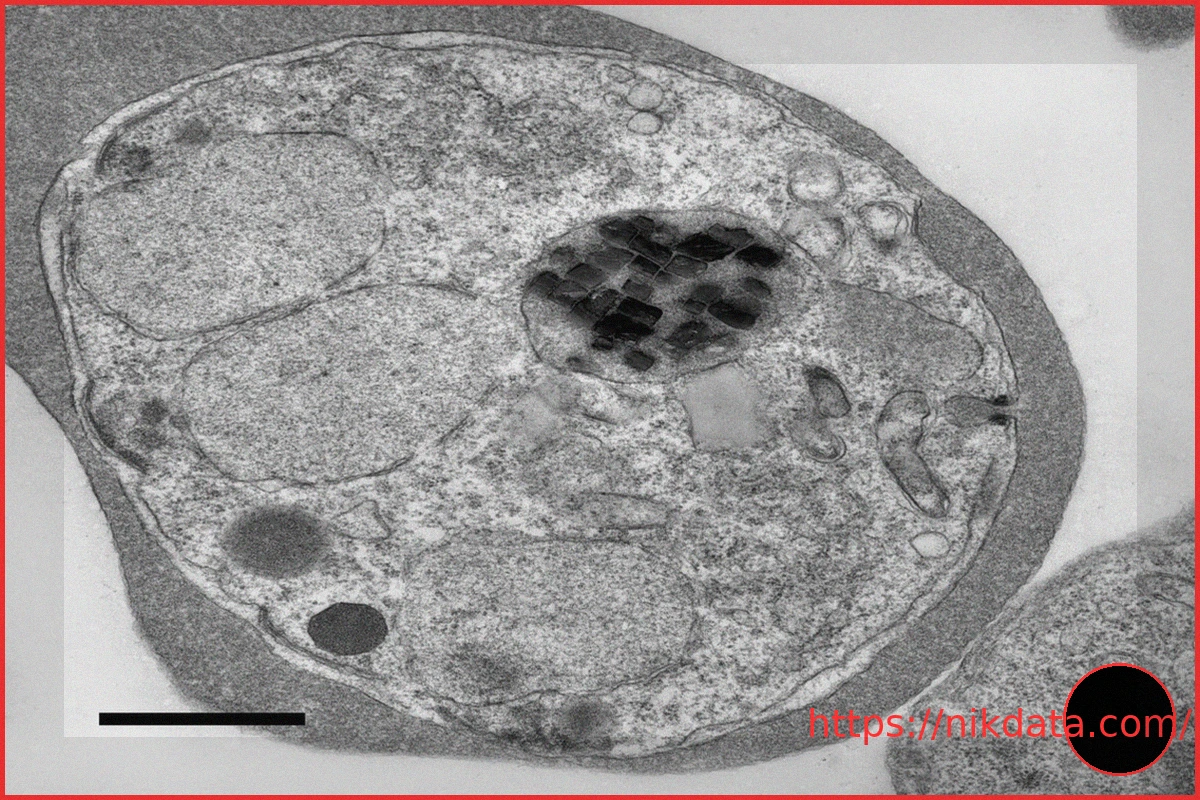

For years, the peculiar, minute spinning crystals observed within malaria parasites have been a source of scientific intrigue and bewilderment. However, groundbreaking new research has finally illuminated their mysterious propulsion mechanism. These tiny structures are, in fact, powered by a unique, rocket-like reaction. This propulsion is achieved through the breakdown of hydrogen peroxide, a process that liberates energy to fuel their continuous movement. Scientists hypothesize that this constant motion isn’t merely a biological quirk; it plays a critical role in the parasite’s resilience and survival, potentially assisting in the detoxification of harmful chemicals and the more efficient regulation of iron within its environment. This remarkable discovery not only paves the way for exciting new developments in anti-malarial drug research but also holds significant potential to inspire novel advancements in the burgeoning field of microscopic robotics.